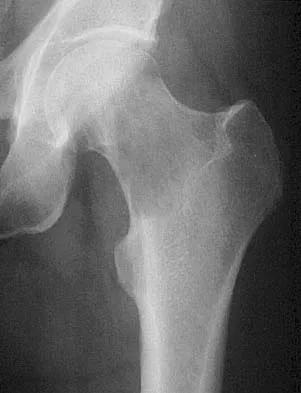

Question 1

A 16-year-old high school football player sustains an injury to the left hip. The avulsed fragment identified by the arrow in Figure 34 represents the origin of which of the following structures?

Explanation